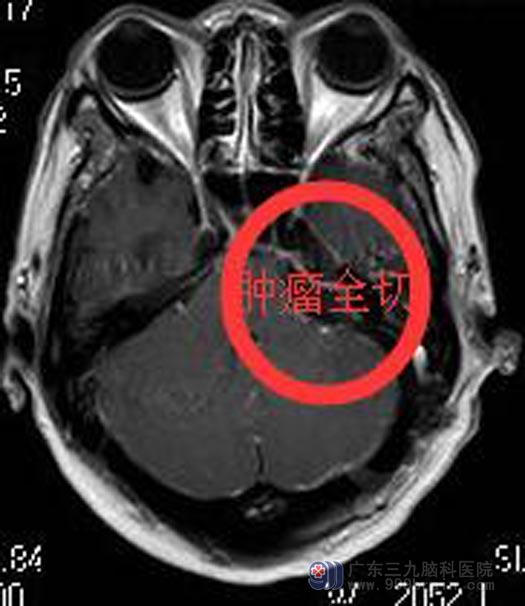

广东三九脑科医院进一步行头颅MR检查提示:左侧桥小脑角区占位性病变,大小约3.8cm×2.2cm×2.1cm,邻近左侧桥臂及脑干受压,四脑室受压变窄,考虑听神经瘤可能。

详细了解病情后,家属同意手术切除。综合神经外科鲁明主任主刀,在全麻下行左侧桥小脑角区听神经瘤切除术,术中显微镜下见肉红色肿瘤组织,包膜完整,被小脑前下动脉包绕,质中,血供丰富,全切肿瘤,面神经、听神经、后组颅神经保留完好。术后陈女士没有出现后组颅神经损害症状,已满意出院。术后病理回报:神经鞘瘤。